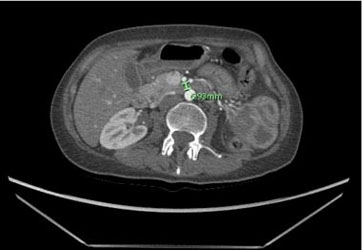

The patient presented intense epigastric pain, vomiting, and constipation, requiring hospitalization. Symptoms subsided when lowering enteral nutrition infusions up to 20 cc/h, and exacerbated when enteral nutrition volume was increased. The physical exam showed a normal abdomen, no distension, soft, with slight sensitivity at the epigastrium and no signs of peritoneal irritation. By this time, the patient’s weight was 36 kg, reaching a body mass index (BMI) of 16.8 kg/m2. An upper digestive endoscopy showed an esophageal stricture with actinic appearance, requiring endoscopic dilation. However, since stenosis does not explain the feeding intolerance, a CT scan was performed. It reported a significant decrease in intra-abdominal fat, especially in the retroperitoneal fat panniculus, associated with a change in caliber and dilation of the second and third portion of the duodenum (Figure 1 and Figure 2), possibly due to partial compression of the third portion between the aorta and the SMA. No other signs of intestinal obstruction were observed. Superior mesenteric artery syndrome was suspected so the images were reviewed with the radiologist, finding an aorto-mesenteric angle of 17° (Figure 3) and an aorto-mesenteric distance of 7.3 mm (Figure 4).

Figure 4: Reduced aorto-mesenteric distance in patient no. 1, transverse view.